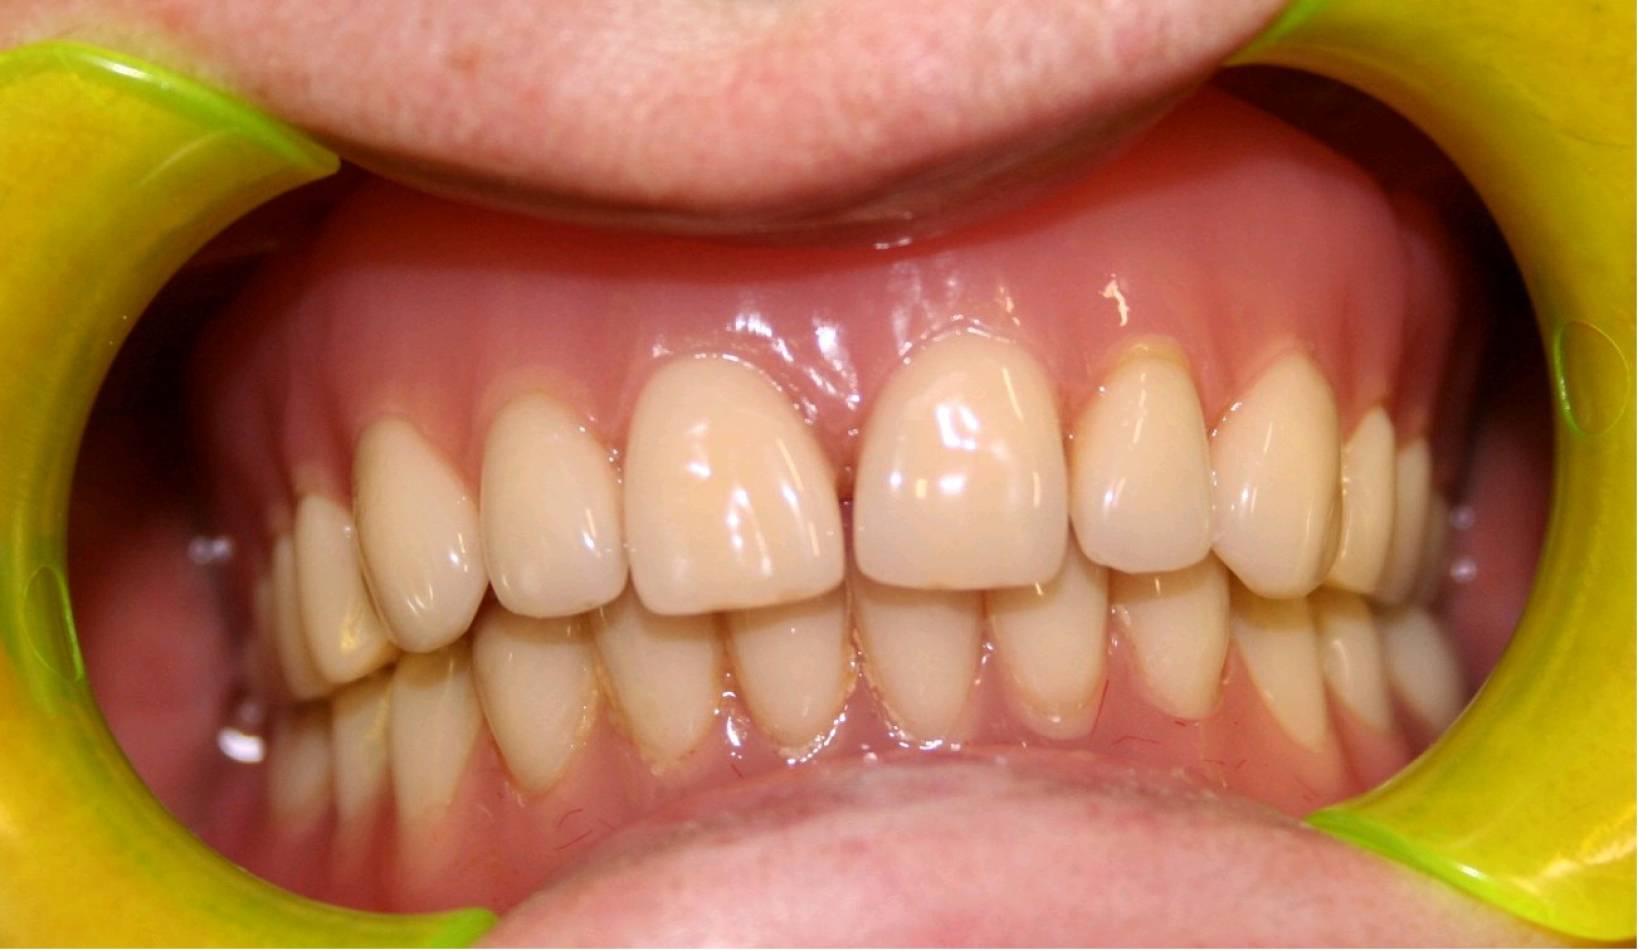

Si effettua implantologia con impianti STRAUMANN e tecnologia IDI EVOLUTION.